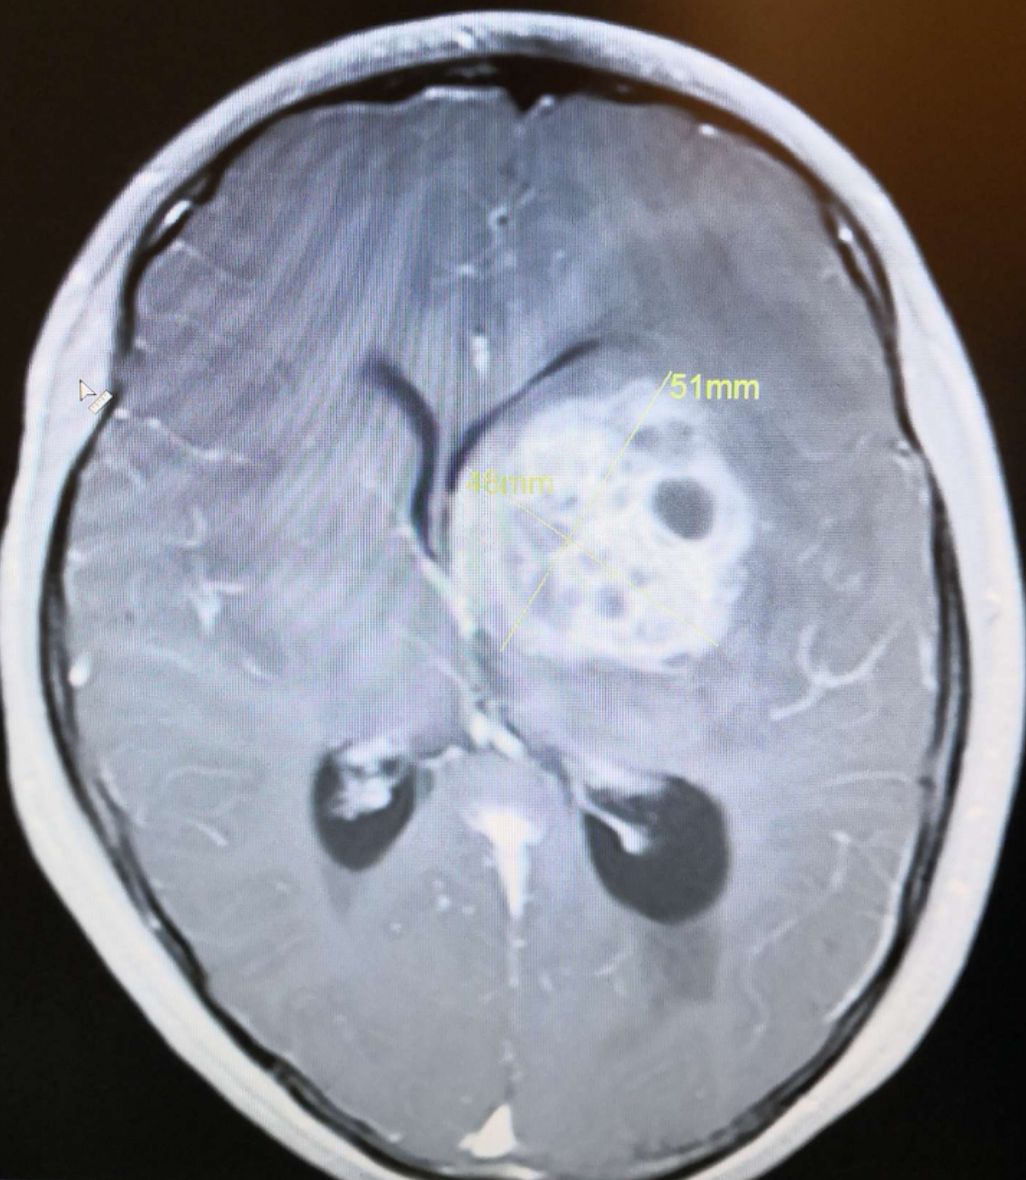

术前头颅MRI T1显示:左侧基底节巨大占位病灶(56*51mm),呈高、低、等混杂信号,脑室受压,中线移位明显。

术前头颅MRI增强扫描显示:病灶强化明显,脑室受压,中线移位明显。

术前头颅MRI 增强扫描显示:病灶强化明显,脑室受压。

术前头颅MRI 增强扫描显示:病灶强化明显,脑室受压,中线移位明显。